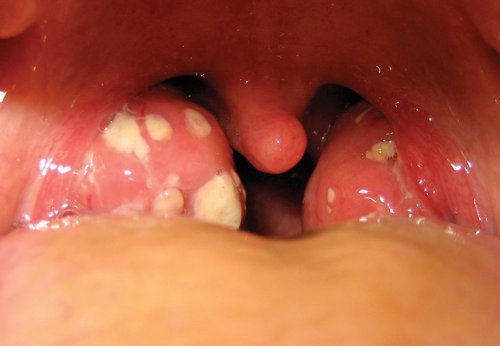

Viêm amidan hốc mủ là tình trạng biến chứng của viêm amidan do điều trị không đúng cách gây nên. Tình trạng này thường kèm theo các triệu chứng khó chịu như có mủ trắng ở amidan, hơi thở có mùi, cổ họng đau rát và làm ảnh hưởng trực tiếp đến sức khỏe và tinh thần của người bệnh.

Viêm Amidan là một dạng bệnh hô hấp phổ biến hiện nay thường kèm theo các triệu chứng như hơi thở có mùi, nóng rát họng, tức ngực khi nuốt. Viêm Amidan nếu không điều trị kịp thời có thể gây ra các biến chứng nguy hiểm như viêm khớp, viêm tai giữa hay viêm cầu thận. Vì vậy người bệnh cần dựa trên các biểu hiện bên ngoài để sớm phát hiện và điều trị nhanh chóng nhất.